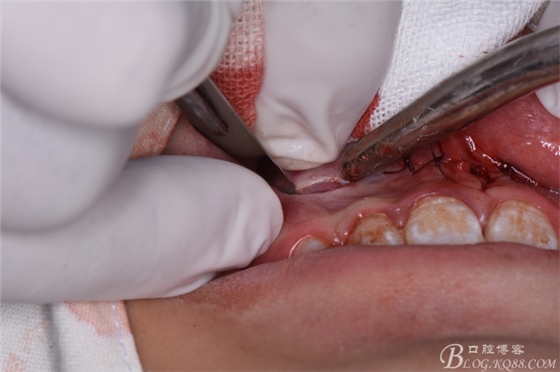

圖22.翻瓣、暴露骨面

圖23.去骨、暴露出鼻底下方的倒置多生牙。